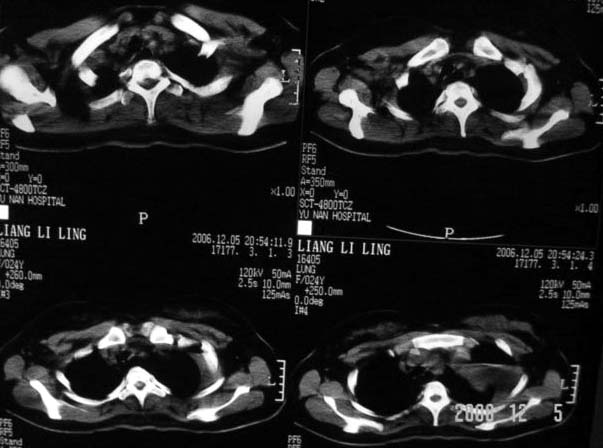

标题: CT5517:女性、24岁,反复胸痛、气促不能平卧半月。 [打印本页]

标题: CT5517:女性、24岁,反复胸痛、气促不能平卧半月。

我看这是膈疝,在纵隔窗第六\\七幅图像上可见胃粘膜影,再者可见两个腔影,这在液气胸是不会有的.

支持膈疝,纵隔窗内可见消化道的内容物。

“反复胸痛、气促不能平卧半月”。+影像学表现=膈疝

谨慎!喝钡透视一下吧。冒然报一液气胸,临床再穿刺引流结果把胃戳个大洞就麻烦了!